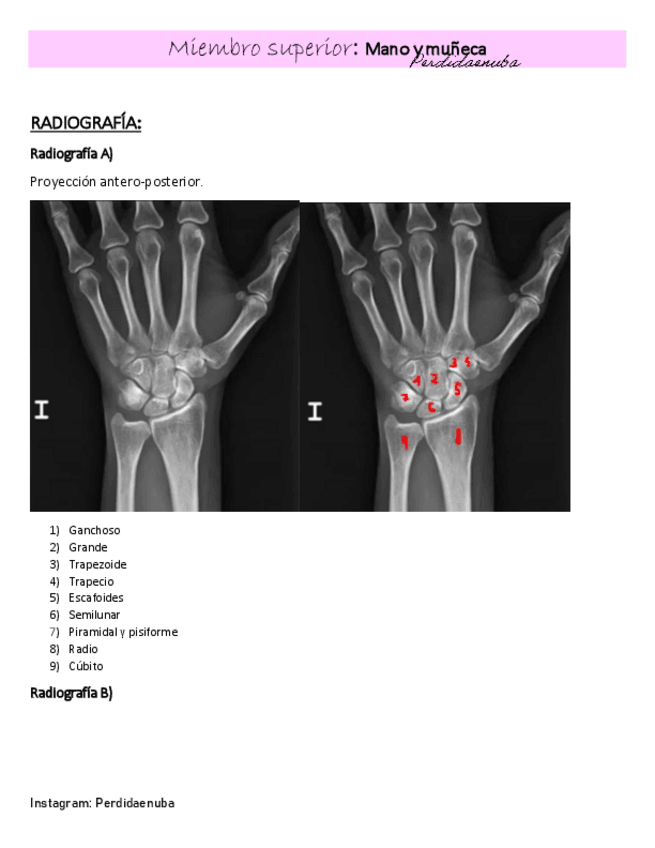

He publicado nuevos apuntes de 8º Cirugía General: MANO-Y-MUNECA.pdf

16 páginas